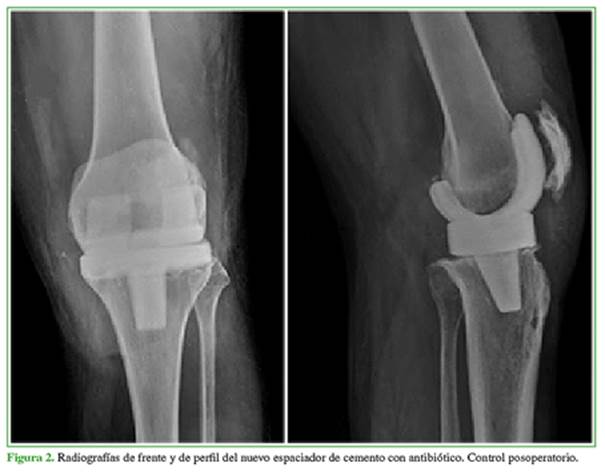

El paciente fue derivado a nuestro Servicio. Con el objetivo de curar la infección, entendiendo la importancia de la cobertura vascularizada, se recambió el espaciador (Figura 2) y se trató el defecto de cobertura con el colgajo neurocutáneo safeno descrito por Masquelet, en el mismo tiempo.

Primer tiempo: se ingresó en la rodilla a través de un abordaje pararrotuliano externo respetando la cicatriz inicial, con desbridamiento del tejido necrótico y el tegumento desvitalizado en la porción anteromedial y el tercio distal de la rodilla. Se recambió el espaciador, y se tomaron seis muestras de tejidos profundos de membrana y hueso, y se enviaron para estudio microbiológico. Se procedió a colocar un espaciador de cemento preformado con gentamicina, y el agregado de cemento con 3 g de vancomicina para complementar los defectos y la cobertura antibiótica local.